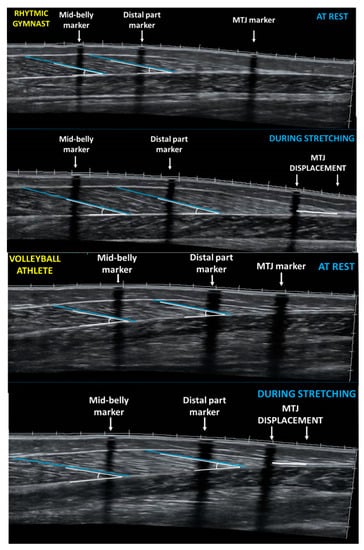

2.3. Gastrocnemius Medialis Architecture and Ankle Joint Angle at Rest

2.4. Gastrocnemius Medialis Architecture and Ankle Joint Angle during Ankle Dorsiflexion Stretching